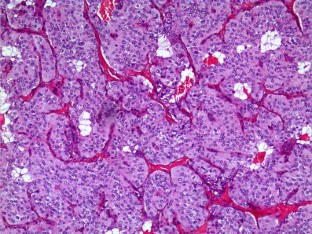

Fig. 1